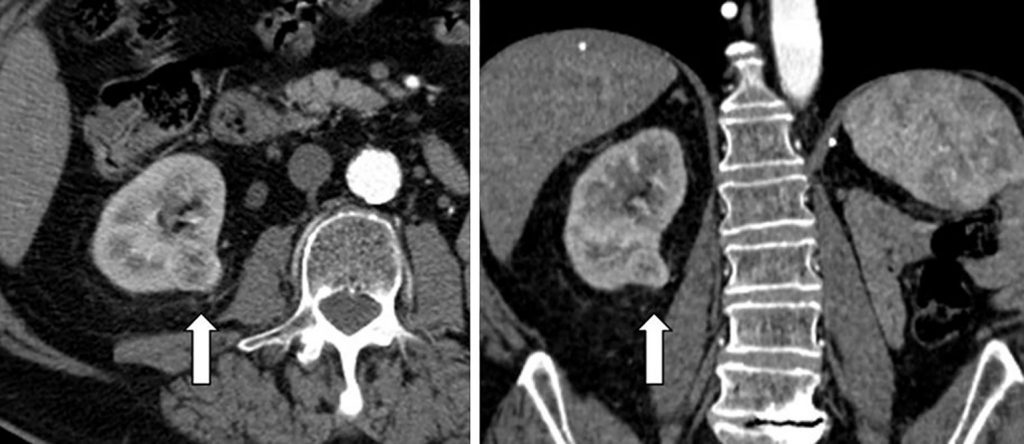

Les autres tumeurs solides, dont les carcinomes, se caractérisent par :

- une échogénicité variable, souvent voisine de celle du rein ;

- une densité tissulaire qui se rehausse après injection.

Les différents types de carcinomes (figures 31.4 et 31.5) et l’oncocytome (deuxième tumeur bénigne rénale la plus fréquente) (figure 31.6) se différencient entre eux par des critères d’imagerie scanner et surtout IRM qui relèvent d’avis spécialisés.

Fig. 31.4 Scanner en vue axiale et coronale d’un carcinome rénal à cellules claires.

Masse tissulaire du rein droit (flèches), hétérogène, rehaussée par le produit de contraste et déformant les contours du rein.

Source : CERF, CNEBMN, 2022.